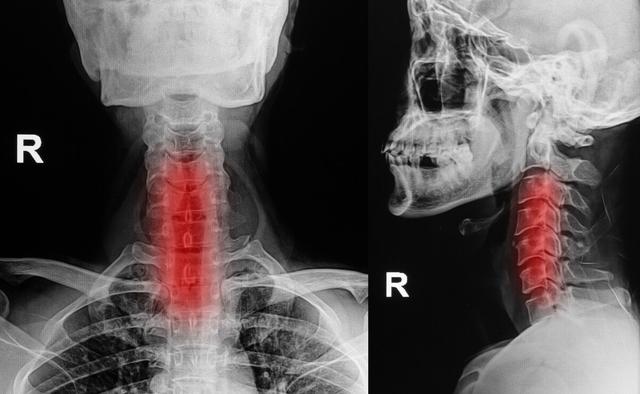

まず、頚椎症

頚椎の変性や頚椎キーボードのヘルニアは神経根や脊髄を圧迫し、手指のしびれや痛みを引き起こし、時には運動機能にも影響を及ぼす。

4.頚椎症

頚椎の肥大や過形成、頚椎椎間板の変性やヘルニアは、頚神経根や頚髄を圧迫し、片側または両側の手指のしびれや痛みを誘発し、それが次第に上腕や前腕に進展し、上肢の運動障害にまで至ることがある。

如中高年特に指先のしびれ。夜間就寝中に悪化する多くは頚椎症が原因である。頚椎症は中高年に多い。骨棘頚椎症の場合、夜寝ている間に肥大した骨によって頚椎神経が圧迫刺激を受け、それが症状を引き起こす。

頚椎症による指先のしびれは、以下のような症状で現れることが多い。発作が続くのステータスを維持することが推奨される。頸椎レントゲン、頸椎MRIなど。さらに原因を特定するための検査。

1.頚椎症

頚椎症患者の種類によっては、指先のしびれも考えられる症状の一つですが、頚椎症患者は指先のしびれ以外にも、上肢や下肢の脱力感、首の後ろの痛み、歩行困難、耳鳴り、首の重苦しさ、めまい、吐き気などの症状を伴うことがあります。頚椎症の診断は難しくなく、整形外科に行ってレントゲン検査をすれば、はっきりした診断がつくかもしれません。

頚椎症 頚椎症

右手のしびれ、神経圧迫症状による頚椎症圧迫の場合は、理学療法マッサージマッサージを行うことをお勧めし、コンピュータの前での長時間の作業、運転などに従事することを禁止し、血圧検査を行うために病院に行くことである状況がある高血圧はなく、頭痛やめまいはありません。

頚椎症、骨棘、椎間板ヘルニアなどは、脊髄から枝分かれする神経根が詰まりやすく、詰まると手のしびれも起こり、手のしびれは胸郭出口症候群と同じような症状が現れます。しかし、手のしびれによって引き起こされるこの症状は、より明らかな頚椎の不快感、こわばり、痛み、活動制限があるでしょう。

指のしびれを引き起こす一般的な病気には、頸椎症も含まれる。

頚椎に問題がある場合、腕神経叢の神経が圧迫されると、手のしびれや手の痛みが生じ、脳への血液供給が不足し、めまいや吐き気を引き起こす深刻な引き金となります。頚椎症による手のしびれは、親指と人差し指のしびれ、小指と薬指のしびれなど、主に片側のしびれとして現れ、ボタンが結びにくい、箸が持ちにくいなど、指の柔軟性が失われます。頚椎症になると、手指のしびれだけでなく、頚部や肩の筋肉痛、上肢の放散痛などを伴うようになります。そのため、片側の手のしびれの症状が出たときには、頚椎症かどうかを警戒する必要があります。

5.頚椎症

頚椎症は頚椎が突出する長期的な要因により、両側の神経や血管を圧迫し、指のしびれの主な原因は神経から腕神経叢神経や頚神経を圧迫することであるため、腕神経叢神経損傷や頚神経叢神経損傷だけでなく、上肢の神経の損傷も指のしびれの原因となります。